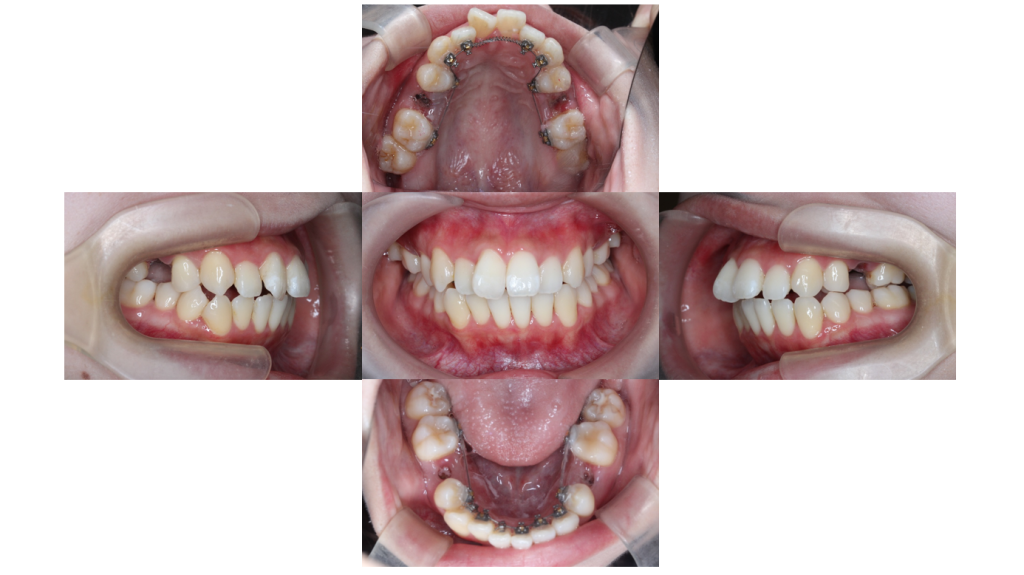

約9ヶ月経過

叢生・裏側全体矯正の症例矯正治療を開始して約9ヶ月が経過しました。

でこぼこも解消され、徐々に歯並びが整ってきました。